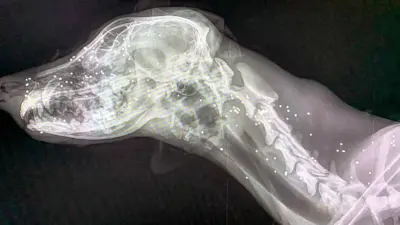

Am Tag darauf ging es gleich ab in die Klinik und die Röntgenbilder bestätigten leider den allerschlimmsten Verdacht: Auf Bringiolina wurde aus nächster Nähe gezielt geschossen. Kopf und Hals sind übersäht mit Bleikugeln, die linke Seite der Schnauze existiert nicht mehr. Für so etwas gibt es keine Worte....

Ein erster Eingriff zur Reinigung der Wunde und Rekonstruktion der fehlenden bzw. gebrochenen Knochenteile hat sofort stattgefunden und Bringiolina konnte am Abend wieder ins ambulatorio zurückkehren.